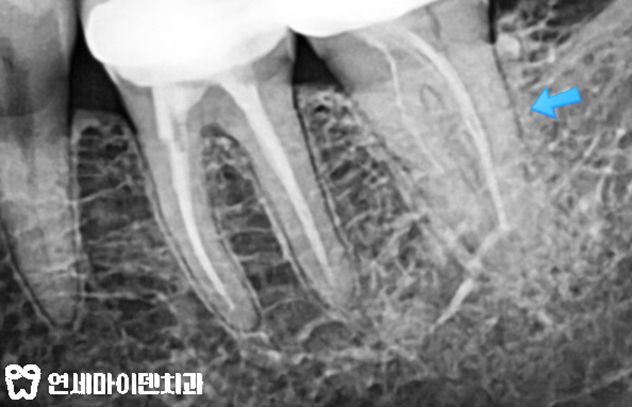

처음 오셨을 때 엑스레이 사진입니다.

화살표 표시가 된 왼쪽 아래 끝 두개의 어금니가 신경치료가 되어 있네요.

저 어금니쪽이 자꾸 뜨거운 물 이시림 증상, 불편한 증상이 있다고 했습니다.

자세히 확인해보니 앞쪽 어금니는 비교적 신경치료가 잘 되어 있는 듯 보이나,,

가장 끝 어금니는 신경치료도 짧아보이고 어딘가 문제가 있어 보입니다.